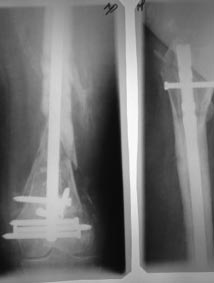

Пациентка 72 лет, сочетанная травма в июле 2011. Одно из повреждений (кроме ЧМТ, грудной клетки, длительной реанимации) перелом дистального бедра.

После временной фиксации в аппарате через 3 недели накостный остеосинтез. Раннее нагноение, попытки консеравативного лечения. Под наше наблюдение попала через 6 месяцев, гнойный свищ по наружной поверхности бедра, до пластины, нестабильная фиксация,миграция винтов, боли, постельный режим. Первым этапом удалена пластина, некрэктомия, бусы из цемента с а\б, апааратная фиксация. Заживление первичное. Вторым этапом снятие аппарта через месяц, замена бус, интрамедуллярный остосинтез, в последующем (через 1,5 месяца) бусы удалены, введены дополнительные винты из-за начинающейся миграции. Заживление первичное. В настоящее время 7 месяцев после последнего вмешательства, гвоздь динамизирован. На фоне улучшения общего состояния (пациенка активизирована, ходи с доп.опорой, болевой синдром незначительный) сохраняются эпизоды гипертермии проходящие на фоне а\б широкого спектра (авелокс). Р-граммы в динамике - отсутствие признаков нестабильности, резорбции, динамизация не исчерпана.Основная проблема - гипертермия, возобновляющаяся через 2-3 недели после прекращения а\б. Варианты:1) Наблюдать до 12-18 месяцев надесясь на консолидацию с последующим удалением 2) некрэктомия? 3) Резекция в пределах здоровых тканей с онкологическим протезом? Другие варианты